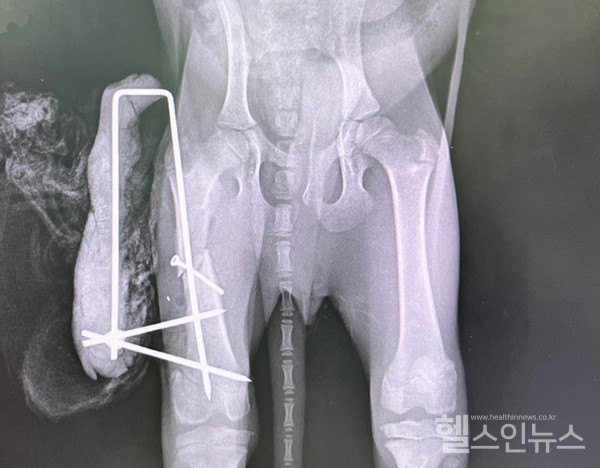

몇 달 전 한 보호소로부터 강아지가 교통사고를 당해 다리가 부러진 것 같으니 수술이 가능하냐는 연락을 받았다. 단순 골절 수술만 필요할 거라고 생각했지만 전혀 아니었다. 골절된 부위는 대퇴골로 골절된 지 2주 정도 되어 보였고 뼈는 조금 붙은 상태였다. 아이의 추정 나이는 3~4개월령으로 뼈의 성장이 계속 진행되고 있었다. 플레이트 수술을 하게 되면 성장에 방해가 되고 나중에 아이가 컸을 때 양쪽 다리에 1cm 정도 단차가 생길 수 있다. 따라서 단차가 생긴 채 붙은 뼈를 다시 떼어내고 제대로 된 위치에 핀을 넣어 잡아 주는 외고정 방법으로 진행했다. 3주 뒤 다시 확인했을 때 아이의 뼈는 잘 붙었고 정상적으로 보행할 수 있게 되었다.

외고정 수술 방법은 내고정 수술법과 반대로 외부에 고정 장치를 장착해 뼈를 지탱하는 방법이다. 피부 겉으로 장치를 빼 고정하기 때문에 불편하다는 단점이 있지만 뼈 주변 조직과 혈관 손상의 위험을 최소화할 수 있고 회복이 빠르다는 장점이 있다.